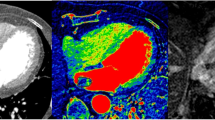

The reviewers also measured the iodine concentration of the masses with the iodine (water) images provided by the workstation. The two radiologists independently measured iodine concentrations (mg/ml) on the same slice with which HU was measured; averaged values were used for analysis. The three modes of images, monochromatic 70 keV images representing post-contrast CT images, MSI images representing pre-contrast CT images, and iodine (water) images could be displayed on the workstation, side by side at the same time, linked together, therefore demonstrating an identical level of the intra-cardiac mass for each mode (Fig. 1). On the workstation, the displayed iodine (water) image provided the quantitative value of iodine (See online Appendix for fundamental equations).

Example image set from a patient with a cardiac tumor. Three modes of images obtained by dual-energy CT data, monochromatic 70 keV image representing post-contrast CT image (a), MSI image representing pre-contrast CT image (b), and iodine (water) image demonstrating identical level of the cardiac tumor were displayed on the workstation (c)

On iodine maps [iodine (water) images], the mean iodine concentration (mg/ml) was significantly different for cardiac myxomas versus cardiac thrombi: 3.53 ± 0.72 for cardiac myxomas versus 1.37 ± 0.31 for cardiac thrombi (p < 0.001) (Table 2; Figs. 2, 3).

An 84-year-old female patient diagnosed with a myxoma. a On the enhanced CT, a 3.2 × 2.5 cm well-defined low-density mass was noted in the left atrium (LA). The CT attenuation value (HU) of the intra-cardiac mass was 82.5. b On the iodine (water) image, the iodine concentration of the mass within the ROI was 3.72 mg/ml

A 49-year-old male patient diagnosed with a thrombus. a On the enhanced CT, a 5.8 × 3.1 cm well-defined low-density mass was noted in the left atrium (LA). The CT attenuation value (HU) of the intra-cardiac mass was 79.8. b On the iodine (water) image, the iodine concentration within the ROI was 1.27 mg/ml